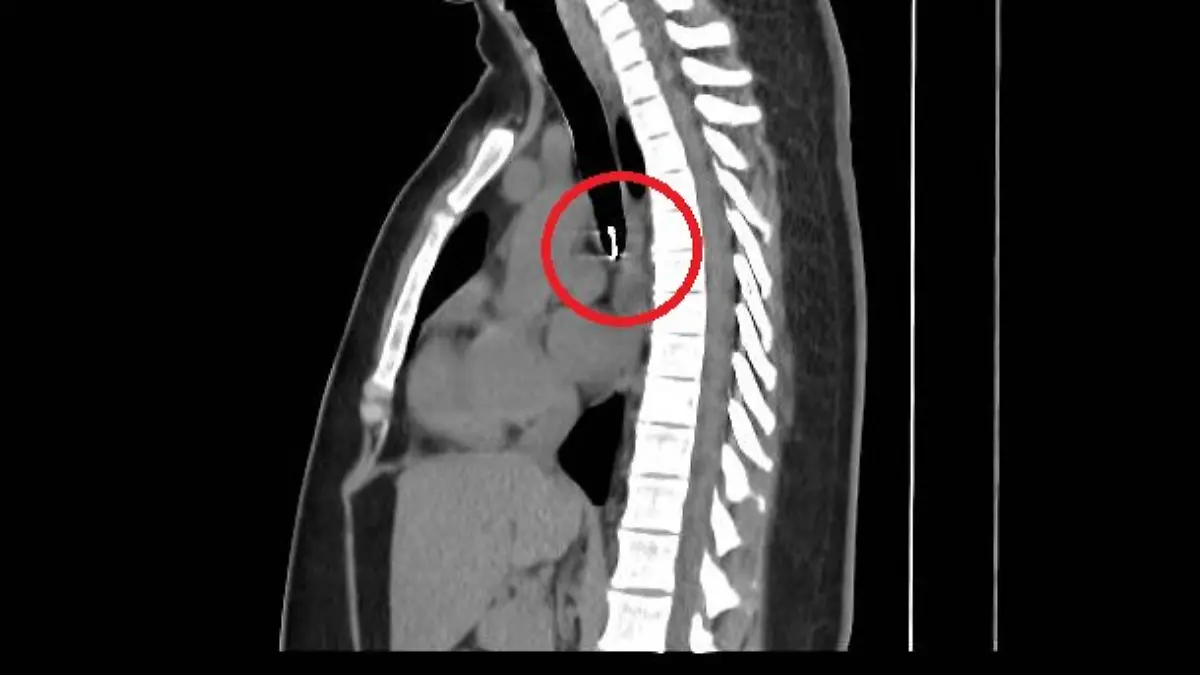

TikTokerin Monica Deyanira Cabrera Barajas wäre beinahe gestorben, nachdem sie unbemerkt ihren Nasenring eingeatmet hatte. Der Ring landete in ihrer Lunge – nur einen halben Millimeter von ihrer Aorta, der Hauptschlagader des Körpers, entfernt. Mehrere Monate lang trug sie den Ring dort.

Die Influencerin aus Mexiko bemerkte zunächst nicht, dass der Ring fehlte, da sie zu Hause viele Nasenringe besitzt. Doch bald begann sie sich unwohl zu fühlen und entwickelte einen chronischen Husten. Als Monica dann zum Arzt ging, folgte der Schock: Ein Radiologe entdeckte das Metallobjekt in ihrem Körper – nur etwa einen halben Millimeter von ihrer Aorta entfernt. Monicas Vermutung: Sie habe das Piercing beim Schlafen eingeatmet.